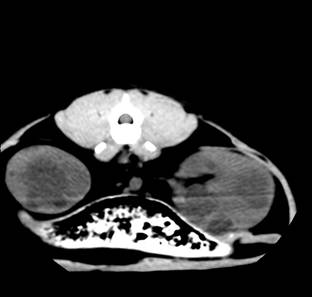

Рис. 9. КТ

кота. Полікистоз нирок у стадії субкомпенсації. Візуалізація миски лівої нирки

Рис. 10. КТ

кота.

Полікистоз

нирок у стадії субкомпенсації. Розширення миски правої нирки (а), кістозні

утворення різної інтенсивності (б, в)

Аналізуючи отримані дані, слід

зазначити, що застосування методу комп’ютерної томографії для діагностики полікистозу

нирок у кішок є можливим. При цьому, використовуючи різні

прийоми та режими сканування, можна отримати дані, що дозволяють

характеризувати контури органа, розмір та вміст кістозних утворень, зміни

ниркової миски. Дослідження в динаміці дозволяє скласти виразну картину

перебігу патології, визначити характер кістозної рідини та зробити висновки

щодо подальшого лікування тварини. Між тим слід зауважити, що застосування

магнітно-резонансної комп’ютерної томографії у ветеринарній медицині в цілому

супроводжується певними труднощами, пов’язаними передусім із відсутністю

відповідного обладнання, тоді як широке використання апаратури у закладах

гуманної медицини не видається можливим з певних міркувань. Таким чином, метод

комп’ютерної томографії є перспективним у діагностиці ниркових патологій у

кішок в цілому, і зокрема полікистозу.